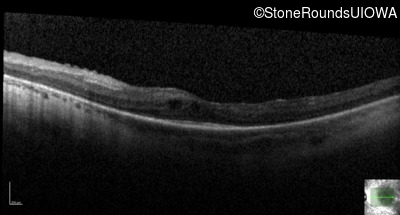

Optical Coherence Tomography - Right - 20/50 -2

Exemplar / OCT Stack

OCT Stack